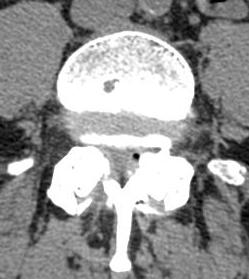

Spesso si assiste ad un quadro clinico di lombalgia cronica di tipo meccanico, che si accentua in posizione eretta prolungata e nella deambulazione, ed invece tende a sparire in posizione supina. In presenza di una concomitante stenosi centrale o laterale, spesso si associano sintomi radicolari, monolaterali o bilaterali. La diagnosi strumentale è essenzialmente radiografica, basata sui radiogrammi standard (fig.10) e dinamici in proiezione laterale (figg.4-5). La TC è comunque utile (fig.11) per evidenziare una stenosi lombare associata (figg.12-13), e per una diagnosi differenziale rispetto alle spondilolistesi istmiche. Anche la RNM ha un ruolo importante (fig.14), potendo evidenziare ernie discali associate (fig.15) o patologie sinovitiche delle articolazioni posteriori degenerate.

• Figura 11

• Figura 12

• Figura 13